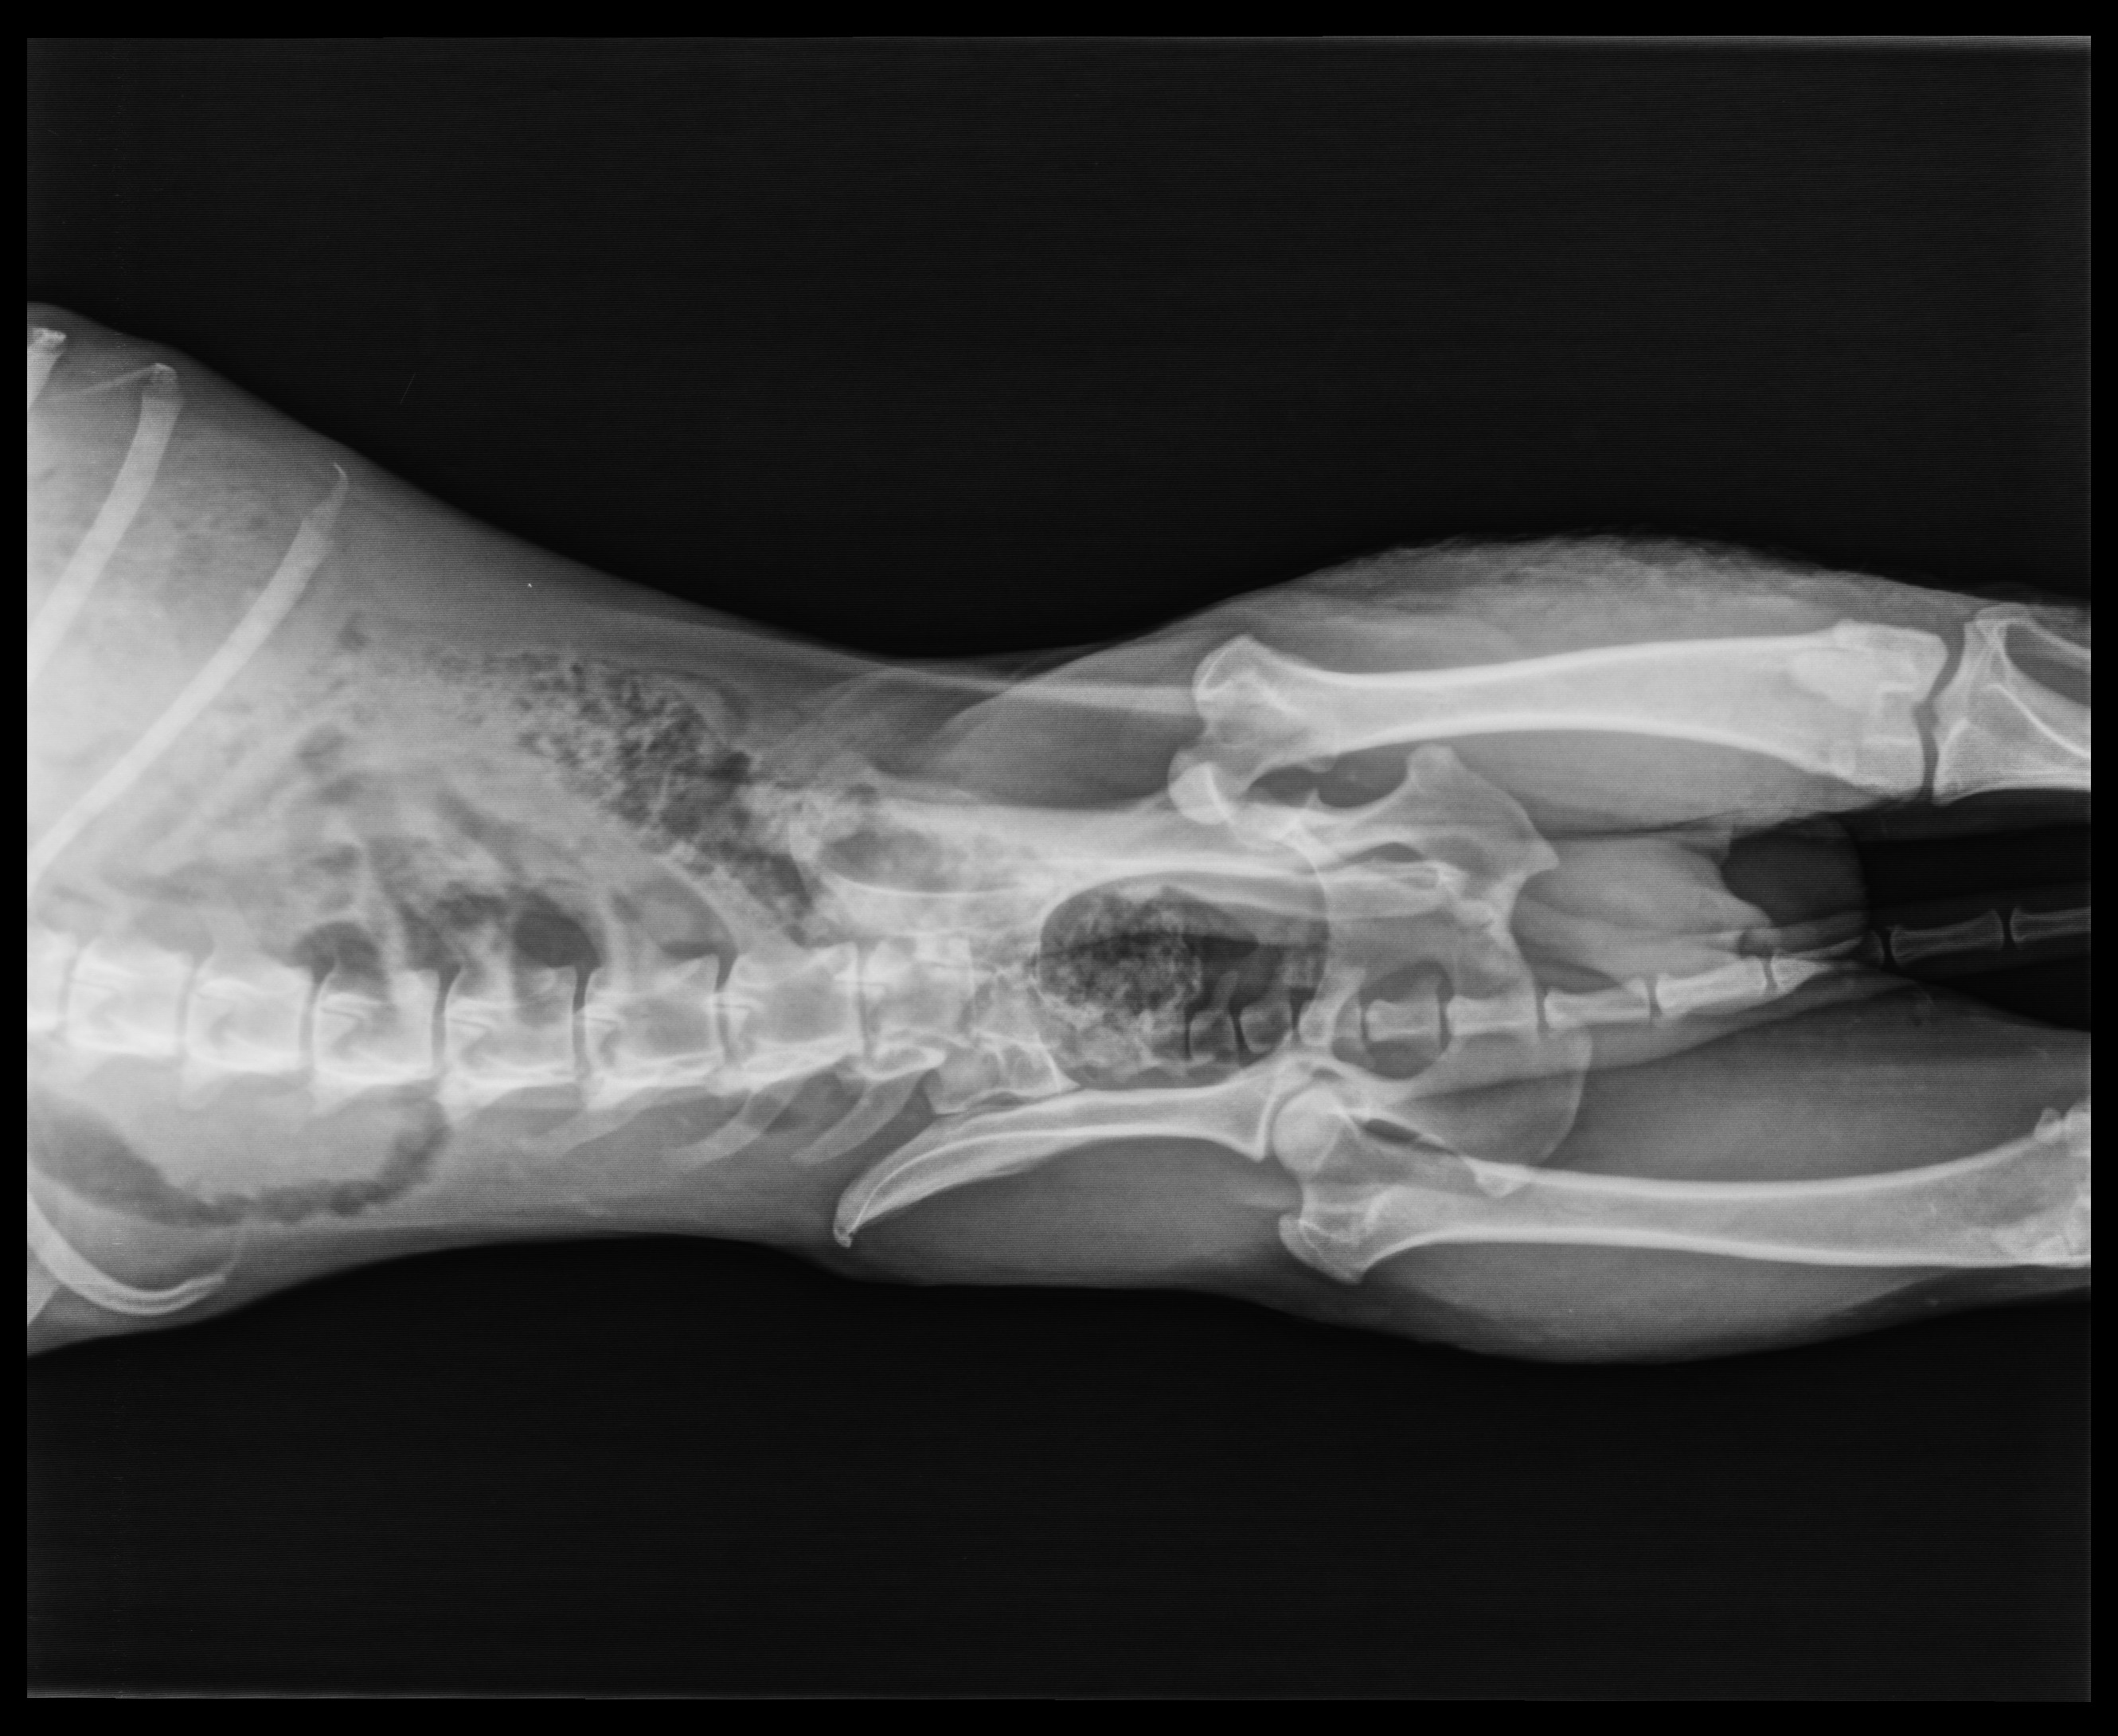

A SEAN le han hecho analitica y radiografias.

Radiografias

Se observa que tiene los pulmones perforados y el torax lleno de aire (de alli la respiración dificultosa) y para eso lo único es reposo.

Tiene la cadera fuera de su sitio y será necesario operación para cortar la cabeza del femur. Estas son las radiografías de SEAN: